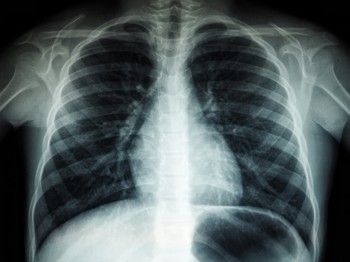

The Cheshire and Merseyside Radiology Imaging Network (CAMRIN) is helping clinicians to detect lung cancer more quickly with the rollout of new AI technology to support the diagnosis of lung cancer.

£1.2m was awarded to Cheshire and Merseyside from the AIDF to accelerate the implementation of an AI imaging and support tool which can analyse chest X-ray images and identify possible signs of lung cancer.

The technology is supplied by Annalise.ai a global health company offering AI solutions for clinicians. Annalise.ai’s technology uses AI to facilitate fast, accurate detection of up to 124 clinical findings and act as a second pair of eyes for clinicians helping them to ensure an accurate diagnosis of lung cancer patients more quickly.